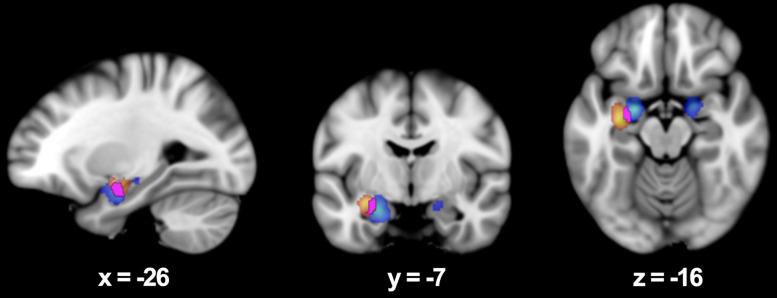

Picture stimuli elicited bilateral activation in the medial parahippocampus, while word stimuli produced left-lateralized activation in the lateral parahippocampus. The overlap analysis identified a shared region in the parahippocampal amygdala. All three contrasts revealed significant activations in key medial temporal lobe (MTL) regions involved in emotional memory, including the hippocampus and amygdala.

图片刺激在内侧海马旁回引发双侧激活,而单词刺激在外侧海马旁回产生左侧化激活。重叠分析确定了海马旁杏仁核中的一个共享区域。所有三个对比在参与情绪记忆的关键内侧颞叶(MTL)区域均显示出显著激活,包括海马体和杏仁核。

结论

两种刺激类型均激活了专门用于情绪记忆编码的内侧颞叶网络。单词刺激选择性地激活了左侧半球侧化的区域,而图片刺激产生了带有向左偏倚的双侧激活。本研究提供了基于情绪刺激类型的海马旁回内侧 - 外侧分化的首个荟萃分析证据。